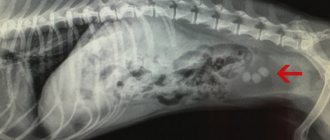

Вторичная форма энтероколита является следствием вирусных, бактериальных, паразитарных или грибковых заболеваний: сальмонеллеза, лямблиоза, гельминтоза, эхинококкоза, парвовирусной инфекции. К развитию этого вида энтероколита могут приводить физиологические патологии кишечника (дуоденальная гипертензия, стеноз кишечника, наличие опухоли), а также нарушения работы иммунной системы.

• Если пес страдает от постоянного жидкого поноса с водой, кровью и слизью, велик шанс гибели на фоне обезвоживания. Шерсть больной собаки становится сухой, кожа утрачивает упругость, в самых тяжелых случаях западают глазные яблоки. При таком течении болезни есть риск выпадения прямой кишки.

• Для многих форм энтероколита характерен сильный метеоризм. Пса ощутимо «раздувает», брюшная стенка напряжена и болезненна.